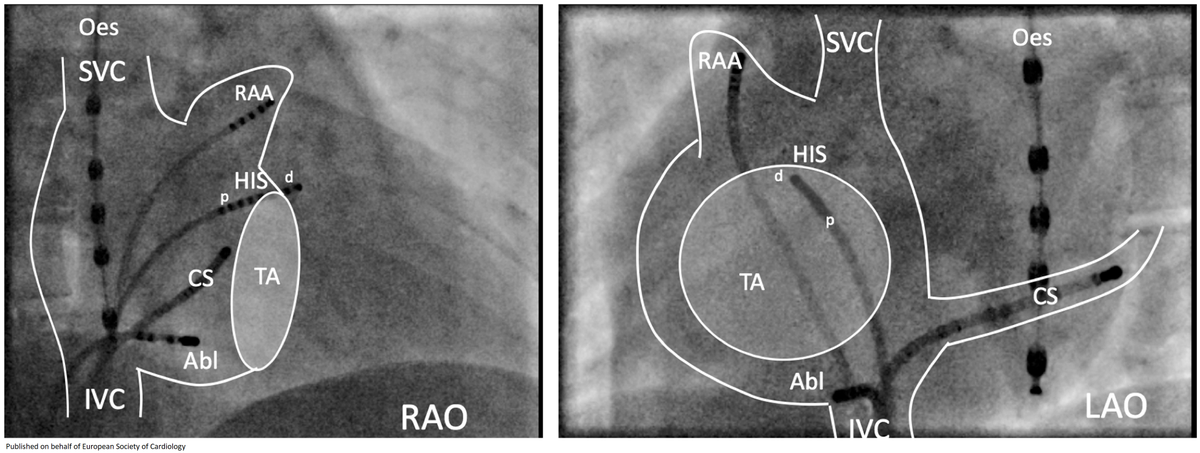

Visualization of the electrophysiologically defined junction between the superior vena cava and right atrium onlinelibrary.wiley.com/doi/abs/10.111… Just a simple message, SVC-RA junction is slanting. The anterior side is higher.

Just a simple message, SVC-RA junction is slanting. The anterior side is higher.